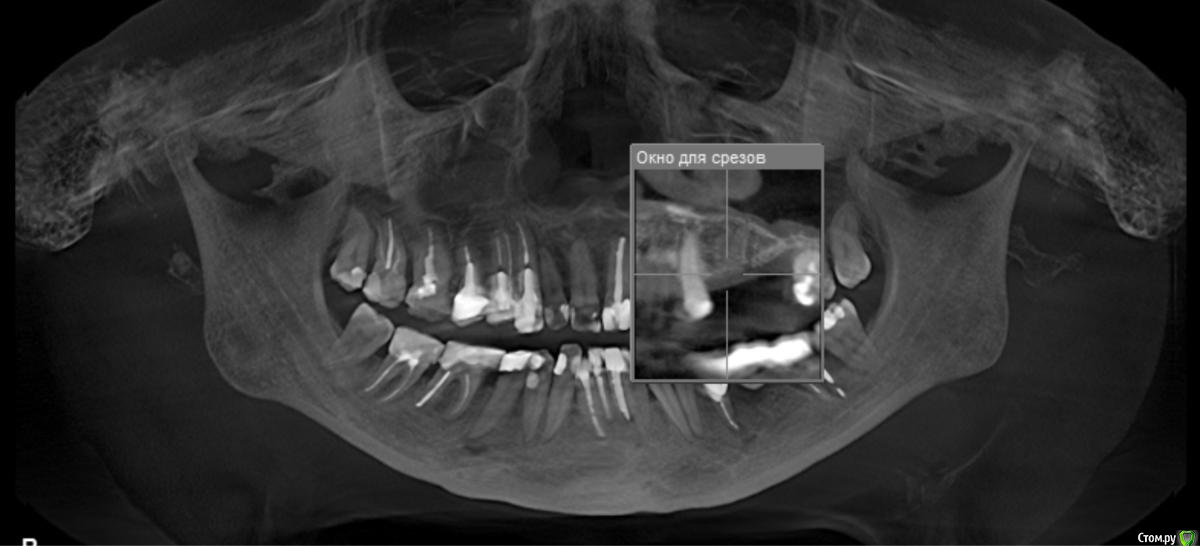

стихия Опубликовано 17 апреля, 2018 Поделиться Опубликовано 17 апреля, 2018 Здравствуйте! 8 месяцев назад были удалены верхняя левая 5-ка и 6-ка из-за кисты. Посмотрите, пожалуйста, мои снимки: возможна ли сейчас имплантация? Хватает ли там костной ткани? Проблема в том, что у меня хронический гайморит, который воспаляется каждый год, не будет ли это причиной плохой приживаемости имплантов? Можно ли при хроническом гайморите делать остеопластику? Буду очень благодарна за ответы. 2 хирурга, у которых была на очной консультации, отказались делать имплантацию в моем случае(( Ссылка на комментарий

колесников Опубликовано 17 апреля, 2018 Поделиться Опубликовано 17 апреля, 2018 (изменено) Дефект гребня в области 27 го зуба будет причиной периимплантного кармана у импланта 26. Я вижу тут 2 варианта: или Имплант Штрауман ТЛ в области 26го с синуслифтингом,+25,либо удаление 27го и мост на имплантах 25-27 Изменено 17 апреля, 2018 пользователем колесников Ссылка на комментарий

Irouil Опубликовано 17 апреля, 2018 Поделиться Опубликовано 17 апреля, 2018 Со стороны пазухи нерешаемых проблем не вижу Ссылка на комментарий